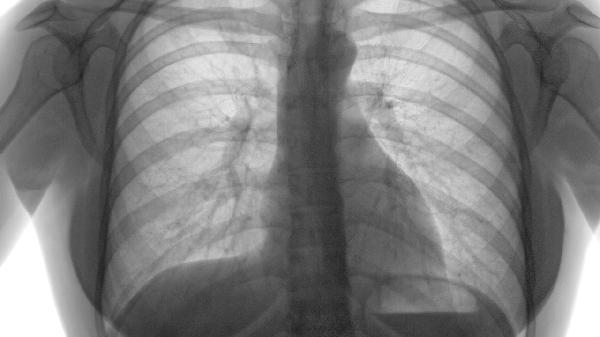

肺气肿患者可遵医嘱使用氨茶碱片、乙酰半胱氨酸泡腾片、布地奈德福莫特罗粉吸入剂、沙美特罗替卡松粉吸入剂、异丙托溴铵气雾剂等药物治疗。肺气肿通常与长期吸烟、空气污染、遗传性抗胰蛋白酶缺乏等因素有关,主要表现为活动后气促、慢性咳嗽等症状。